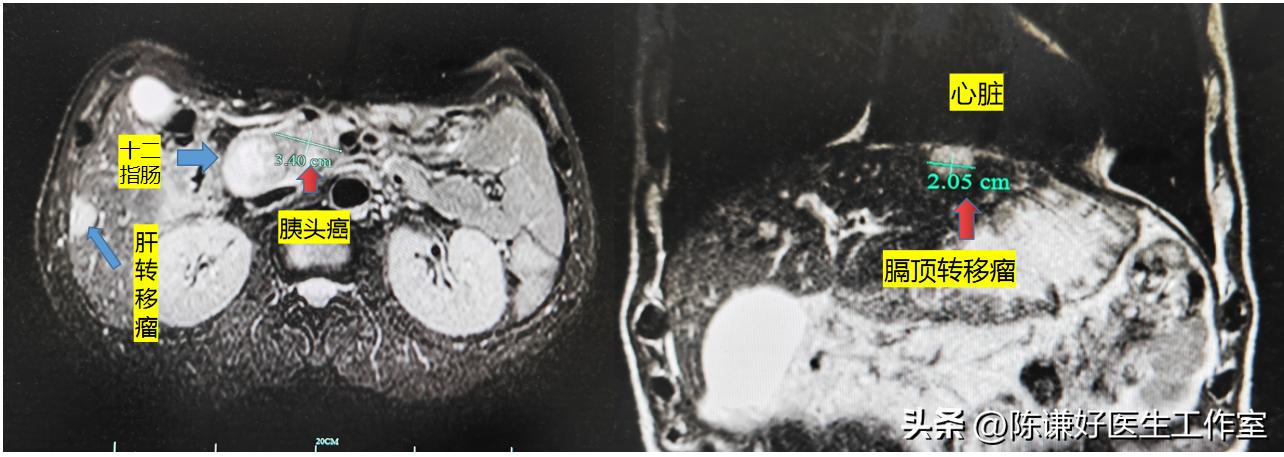

病人术前磁共振显示肿瘤发展迅速,肝内已经有多发转移,这种临床一般诊断为晚期胰腺癌,目前国内大多数医院主要治疗方案是以化疗为基础,然后联合肝动脉灌注化疗,靶向免疫治疗。但是大多数效果均不理想,一般中位生存期在3-6个月左右。

病人术前磁共振图像

肝膈顶转移瘤海扶刀治疗前后对比

这个病人尤其特别的是,患者肝转移瘤位于膈顶,靠近心脏,如果选择传统的治疗方法,很难处理,即使使用微创的射频消融或者微波消融,损伤膈肌和心脏的风险比较高,而海扶刀治疗属于微无创治疗方法,对这些特殊部位的肝转移瘤也能进行很好的消融。